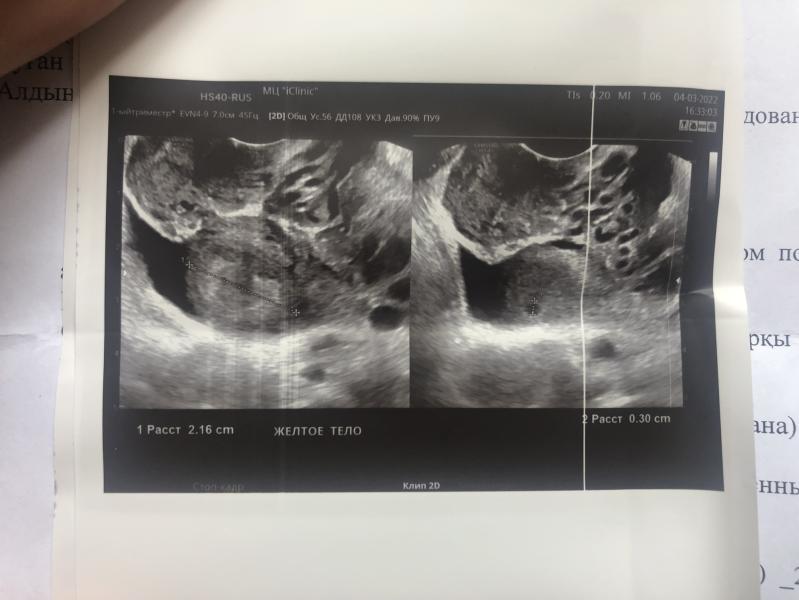

Вчера узнала что беременна, так как у меня не было месячных с 2019 г (была беременна, кормила, отучила от груди 2 мес назад) хотела подтвердить беременность и узнать сколько недель! Сделала УЗИ в матке и в трубах нет, мин 30-20 искали и нашли в левом яичнике желтое тело 2,6 см. И теперь предполагают, что это внематочная яйчнековая беременность! Тесты показывают с каждым днем ярче 2 полоску. У кого так было? Есть ли вероятность, что оно спуститься в матку?